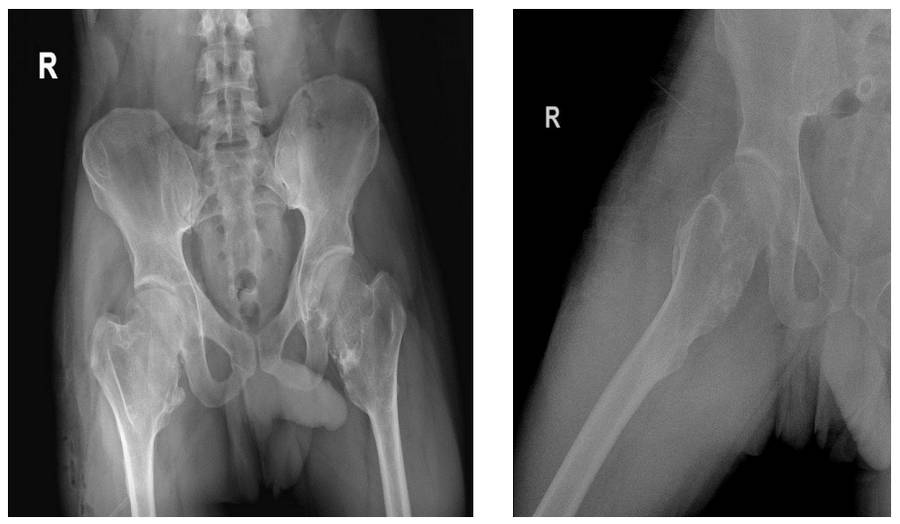

Before the surgery: X-rays show widespread osteochondromas around the hip and knee.